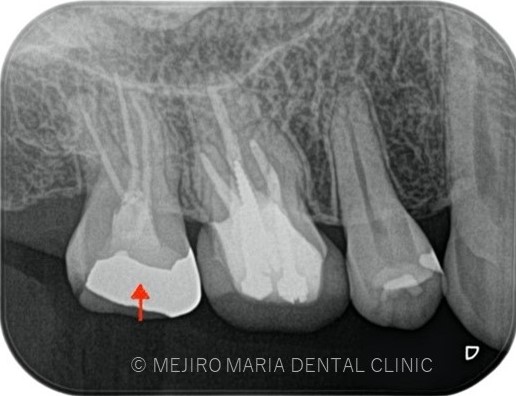

右上7番には臨床症状(叩くことでの痛み)が確認できるものの、レントゲン上には根尖性歯周炎と判断できる透過像(病変の影)は確認できませんでした。歯科用CTを撮影してみると、近心根と遠心根に明らかな病変を認めました(歯科用CT画像1赤丸)。他の臨床症状と歯科用CT画像から右上7番の根尖性歯周炎と診断しました。

また、同時に近心根には見逃している根管もしくはフィンと言われる極小なスペース(CT画像2赤丸)が存在することも確認できます。